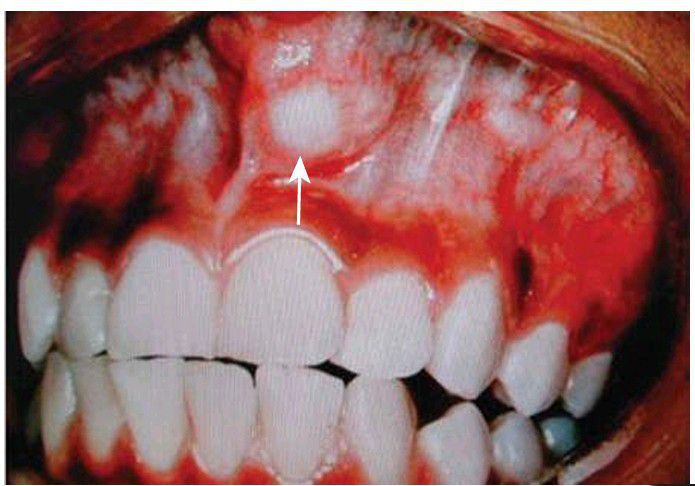

Monomorphic adenoma

Monomorphic (canalicular) adenoma of the left upper lip or vestibule (arrow).